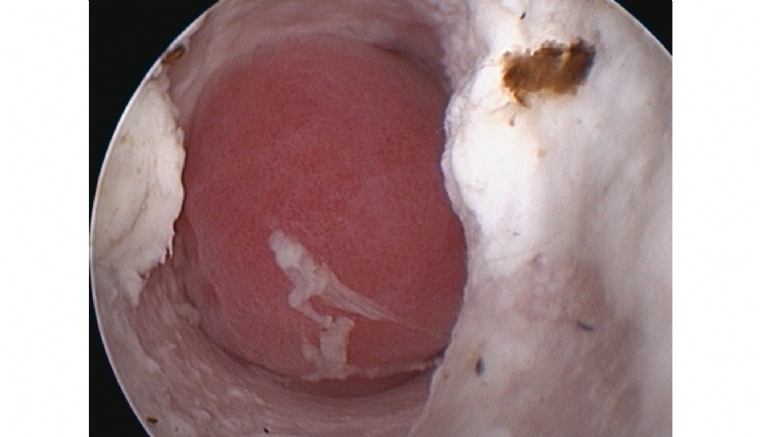

Aspect typique d'un polype dans le conduit horizontal chez un chat.

© Emmanuel Bensignor